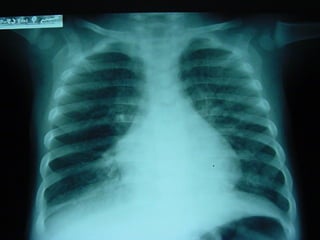

Clínica Radiología: Patrón alveolar. Opacidad Broncograma aéreo Poca o ninguna pérdida de volumen Problemas.  Sólo se condensa aquello que cumple dos condiciones: Suficientes leucocitos: pus Parénquima relativamente normal. No hay condensación clara en enfisema, bronqutis crónica, destrucciones cicatriciales y bronquiectasias. Aparición de derrame: Paraneumónico: iritativo, estéril o empiema, infeccioso Metaneumónico.

Clínica Radiología: Patrónalveolar. Opacidad Broncograma aéreo Poca o ninguna pérdida de volumen Problemas. Sólo se condensa aquello que cumple dos condiciones: Suficientes leucocitos: pus Parénquima relativamente normal. No hay condensación clara en enfisema, bronqutis crónica, destrucciones cicatriciales y bronquiectasias. Aparición de derrame: Paraneumónico: iritativo, estéril o empiema, infeccioso Metaneumónico.